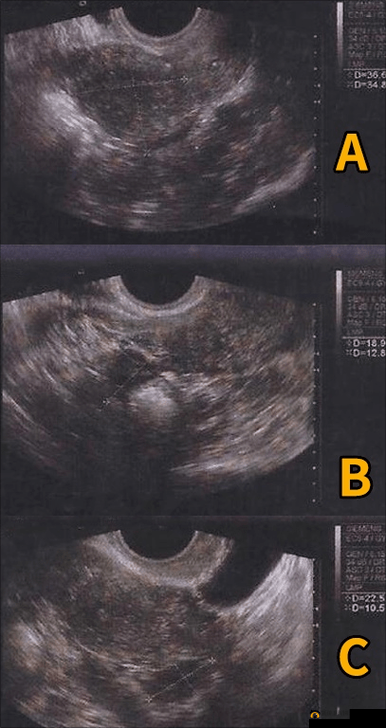

B 超,也就是黑白超声,虽然图像是黑白的,但它在观察胎儿的形态、大小、胎位等方面也能提供重要的信息。而且 B 超的价格相对较为亲民,操作也较为简便。qks热门主流游戏攻略_实用技巧_经验分享

在怀孕早期,一般医生会建议先进行 B 超检查。这是因为在孕早期,胎儿的器官发育还不完全,B 超就足以满足对孕囊、胎芽、胎心等基本情况的观察需求。而且此时胎儿较小,彩超的优势尚未充分体现。qks热门主流游戏攻略_实用技巧_经验分享

到了怀孕中期,特别是 20 - 24 周左右的大排畸检查,很多医生会推荐准妈妈进行彩超检查。这个阶段,胎儿的各个器官已经基本发育成型,彩超能够更全面、更细致地对胎儿进行筛查,及时发现可能存在的结构异常。qks热门主流游戏攻略_实用技巧_经验分享